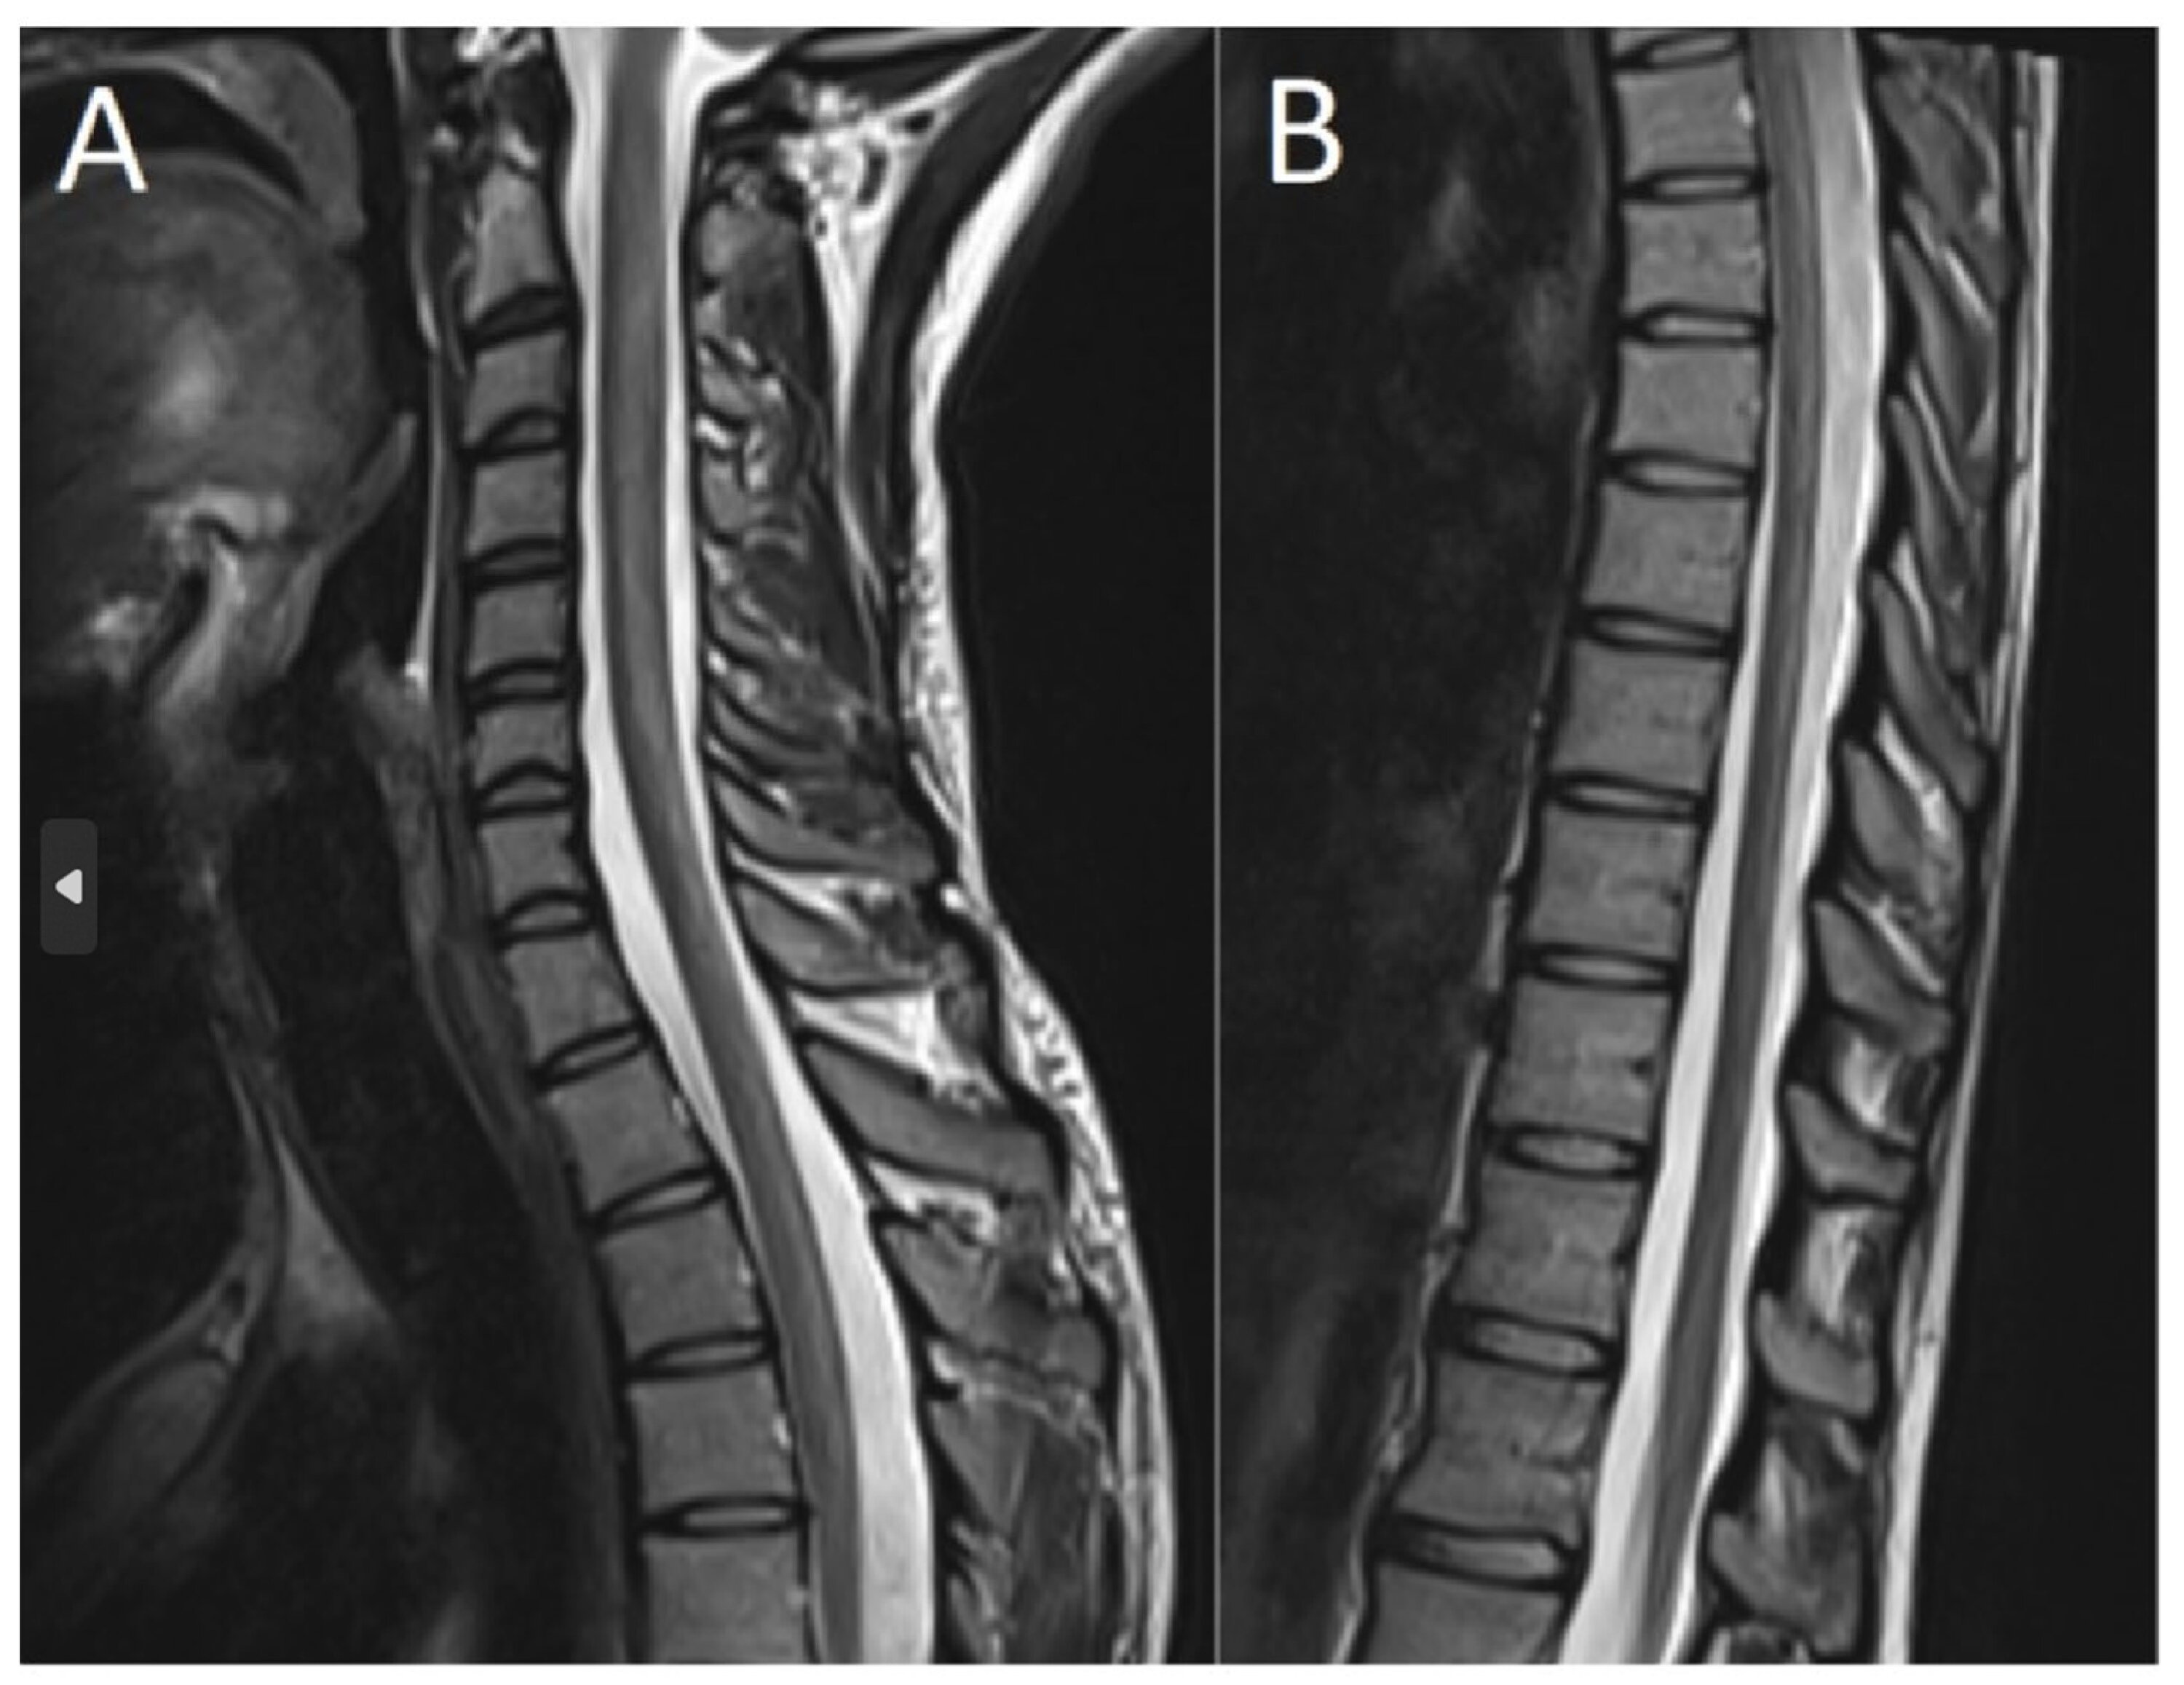

MRI scans confirmed damage to the posterior column of the cervical spinal cord, specifically from the second to the sixth cervical vertebra. Dr. Hoang Anh Tuan, a neurology specialist at Medlatec Hospital, stated that this type of spinal cord damage is characteristic of prolonged nitrous oxide abuse. Dr. Tuan explained that extended exposure to N2O gas deactivates vitamin B12 in the body, leading to this spinal cord damage, with early symptoms often presenting as numbness in the hands and feet.

The prognosis for the patient's recovery is good, provided the treatment plan is strictly followed, due to the early diagnosis. Dr. Tuan stressed that if not detected in time, severe nerve damage can result in slow or no recovery. The patient is currently receiving outpatient treatment and will undergo regular follow-up visits, including MRI scans after three to six months, to monitor the recovery of the cervical spinal cord damage.